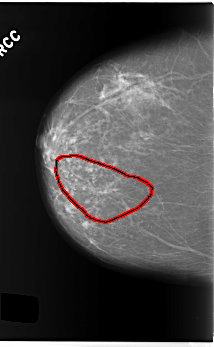

C_0214_1.RIGHT_CC

RIGHT_CC LINES 5888 PIXELS_PER_LINE 3624 BITS_PER_PIXEL 12 RESOLUTION 50 OVERLAY

FILE: C_0214_1.RIGHT_CC.OVERLAY

TOTAL_ABNORMALITIES 1

ABNORMALITY 1

LESION_TYPE CALCIFICATION TYPE PLEOMORPHIC DISTRIBUTION SEGMENTAL

ASSESSMENT 4

SUBTLETY 4

PATHOLOGY MALIGNANT

TOTAL_OUTLINES 1

BOUNDARY